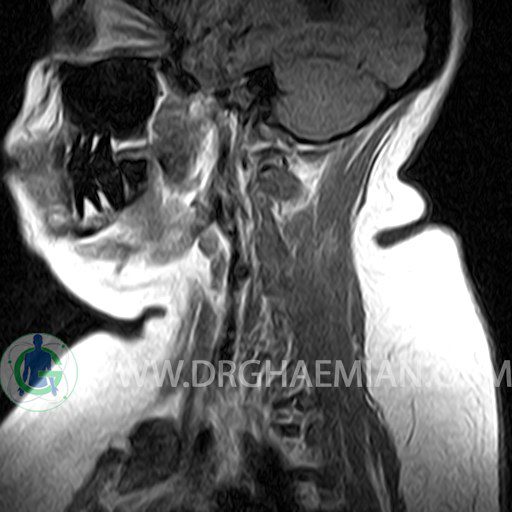

ام آر آی گردن با استفاده از انرژی آهنرباهایی قوی نصاویری از قسمت ستون فقرات که از گردن (ناحیه گردن ستون فقرات) عبور می کند، ایجاد می کند. ام آر آی از تشعشعات استفاده نمی کند. در این کیس کیفوز گردن و دیهیدراته و بیرون زدگی مهره های C3/C4/C5/C6/C7 دیده می شود.

CERVICAL SPINE MRI

(Without contrast)

Technique : Sagittal T1 , T2 , Axial T2 .

– Change of cervical lordosis to mild kyphosis

– C3/C4/C5/C6/C7 discs dehydration & bulging

are seen